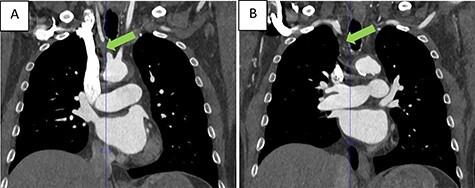

Multimodality imaging in subclavian steal syndrome.

Subclavian steal syndrome is a rare vascular cause of recurrent effort-related syncope events, affecting ~2% of the general population. Here, we report a case of a 64-year-old male who was hospitalized because of recurrent effort-related syncope events. Physical examination revealed several characteristic clinical clues for subclavian steal syndrome. Indeed, through the use of multimodality imaging, the diagnosis was established. We demonstrate that the combination of history taking, thorough physical exam and subsequent imaging studies can establish a relatively rare diagnosis of recurrent syncope.